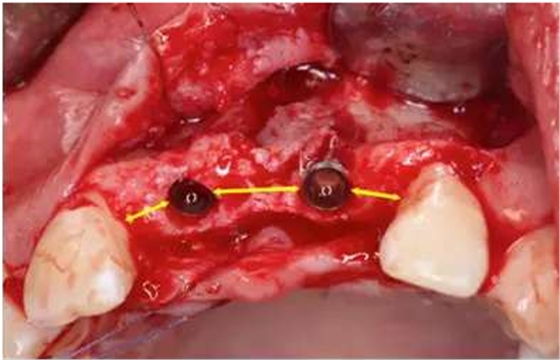

做牙槽嵴頂切口及22牙遠(yuǎn)中附加切口,翻瓣;

在11、21位置植入兩顆NobelActive 3.5mm*13mm種植體;

種植體頰側(cè)骨缺損處植入Bio-Oss骨替代品

覆蓋雙層Bio-Gide膠原膜